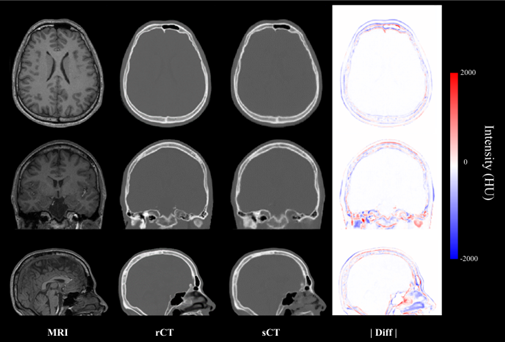

과학기술정보통신부는 한국과학기술연구원(KIST) 바이오닉스연구센터 김형민 박사 연구팀이 MRI 영상을 기반으로 CT 영상을 생성해내는 인공지능(AI) 기술을 개발했다고 2일 밝혔다. 연구팀은 모의실험을 통해 MRI만으로도 ‘경두개 집속 초음파’ 시술이 가능하다는 것을 검증했다. 이번 연구결과는 의료 정보 분야 국제 학술지인 IEEE에 게재됐다.

경두개 집속 초음파 시술은 두개골을 열지 않고 초음파 에너지를 뇌의 특정 영역에 전달해 수전증 등 퇴행성 운동장애와 정신질환을 치료하는 방법이다. 두개골을 통과한 초음파의 초점이 뇌 병변에 정확히 맺혀야 해 CT가 필수적인 시술 중 하나다. 자성을 이용하는 MRI와 달리 CT는 방사선으로 단단한 신체부위를 투과해 선명한 모습을 볼 수 있기 때문이다. 하지만 연구팀은 MRI로 얻은 영상을 자체 개발한 ‘3차원 조건부 적대적 생성 신경망 모델’ AI기술로 CT 영상처럼 변환시켰다. 변환된 합성 CT를 이용한 시술도 성공적이었다. 방사선에 노출되는 CT를 찍지 않아도 AI로 MRI 영상을 변환해 시술이 가능해진 것이다.